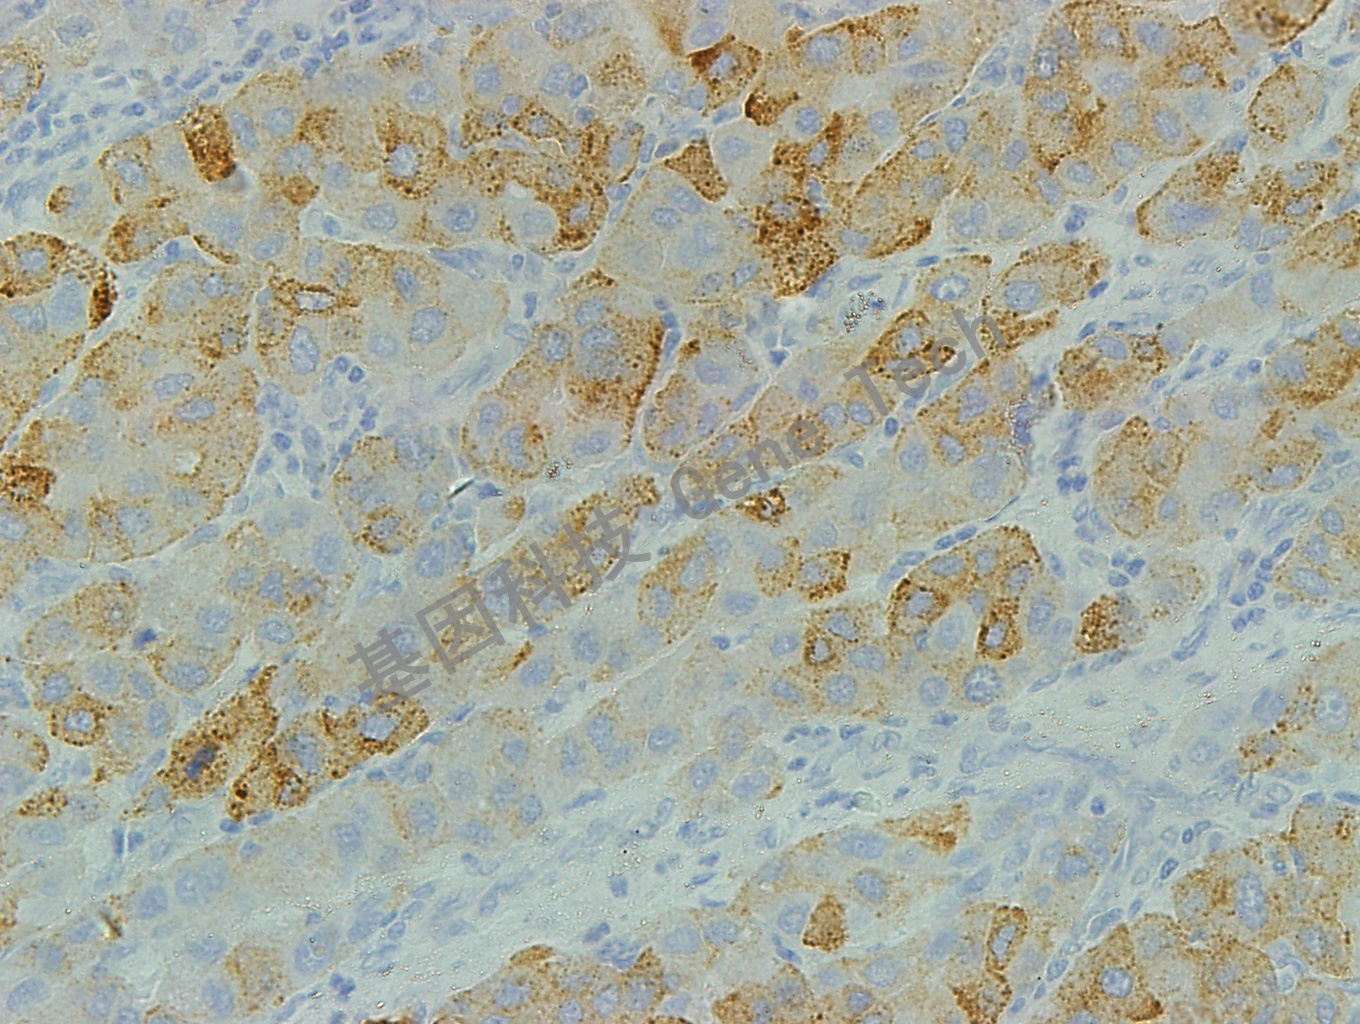

肝石蜡切片,用 CD71(GT2143)染色,细胞膜/细胞浆阳性,DAB显色。(40×)